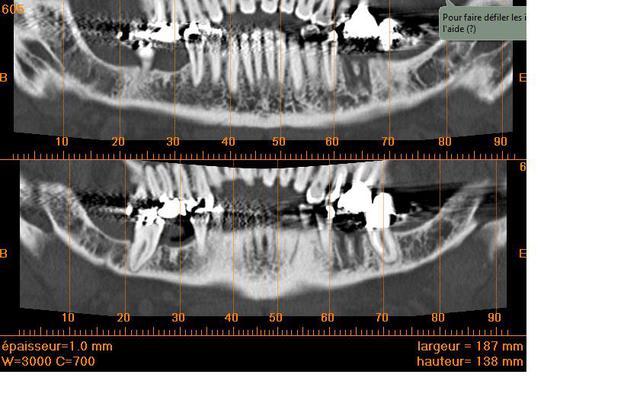

Deux implants en 36 46 et j'espere vous avoir donné les bonnes coupes sinon cela veut dire que je n'ai rien compris !!!

j' ai fais des mesures avec le logiciel pour un implant de 12 mm

sur les bonnes coupes je l'espere ;)

Attention tout de même pour 36 : os de très mauvaise qualité (type 4) voir cicatrisation fibreuse...... j'ai perdu un implant récemment, l'image était très radioclaire...il faut en informer le patient. Commence par 46.

romdenice

hé ho, l'exo de 36 remonte à début juin, il est normal d'avoir une telle image

car il faut au moins 200j pour avoir un minéralisation complète et un aspect radiologique "normal".

à 3 mois par contre, au forage on a déjà du bon nonos et encore du potentiel de cica (en tout cas supérieur à la zone 46 si il n'y a pas eu passage d'ostéotenseur...) et une résorption vestibulaire encore limitée